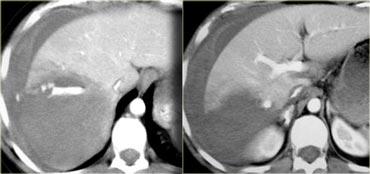

Trước tiên hãy quan sát các hình ảnh bên trái của bệnh nhân bị chấn thương gan.

Các dấu hiệu CT trong trường hợp này là gì?

Các dấu hiệu bao gồm:

- Mất tưới máu hoàn toàn thùy gan phải.

- Vùng ngấm thuốc cản quang (contrast blush) trong nhu mô gan, đồng thời lan ra ngoài bờ bên của gan.

- Tràn máu ổ bụng (Hemoperitoneum).

- Một vùng ngấm thuốc cản quang thứ hai ở mức thấp hơn.

- Tụ máu dưới bao gan lớn hơn 10 cm (tức là tổn thương độ 4)

- Vùng ngấm thuốc cản quang (contrast blush) (mũi tên)

- Không có tràn máu ổ bụng kèm theo

Vì vậy, mặc dù có thoát thuốc cản quang, bệnh nhân này sẽ được điều trị bảo tồn (không phẫu thuật) và có thể có tiên lượng tốt, do không có chảy máu vào khoang phúc mạc.

Thoát thuốc cản quang có ý nghĩa đặc biệt quan trọng, nhất là khi kết hợp với tràn máu ổ bụng.